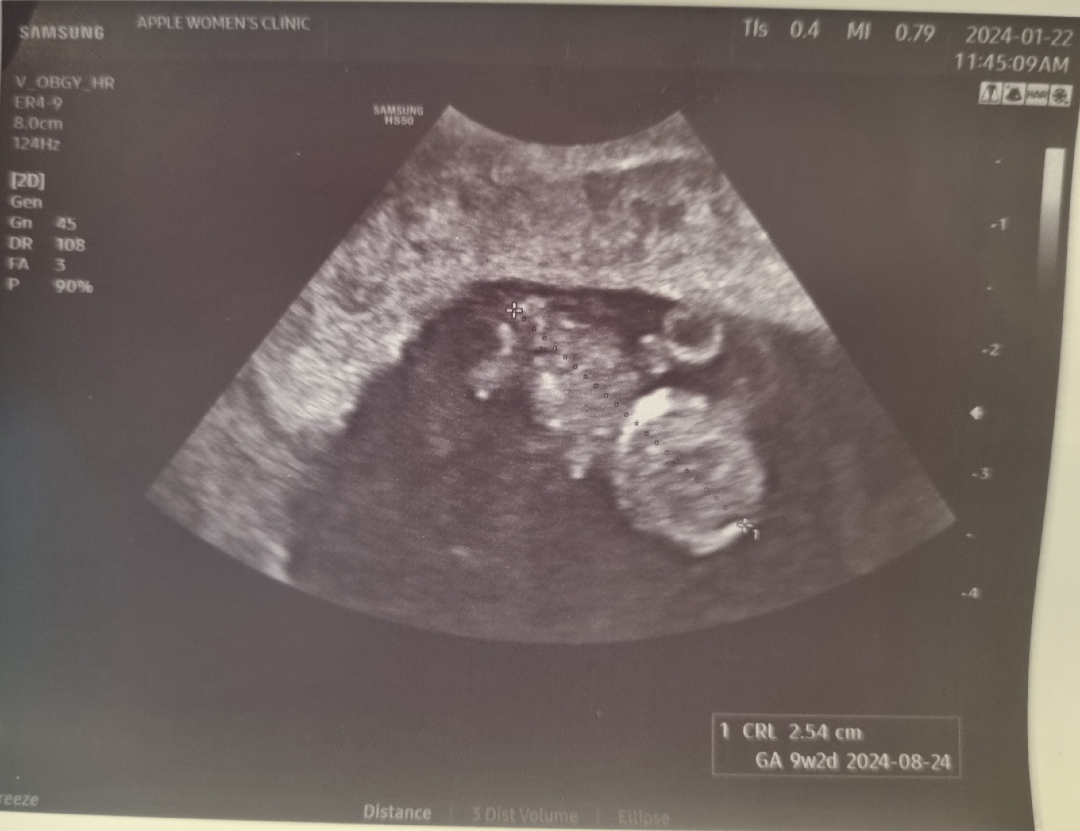

안녕하세요~ 눈팅만 하다가 처음 글 올려봅니댜..ㅎㅎ 9주 2일차 산전검사 결과 들으러 갔다가 잘있나~ 보고 왔어용 ㅎ.ㅎ 너무 귀엽게 잘있죠ㅠㅠㅠㅠㅠ? 검사결과 다행히 다른건 다 괜찮다고 나왔는데 비타민D가 부족하다고 2000씩 복용하라 하셔서 하나 받아왔네욥...ㅎㅎ 모두모두 건강 잘 챙기시면서 힘내시구 행복한 나날들 되세요♡